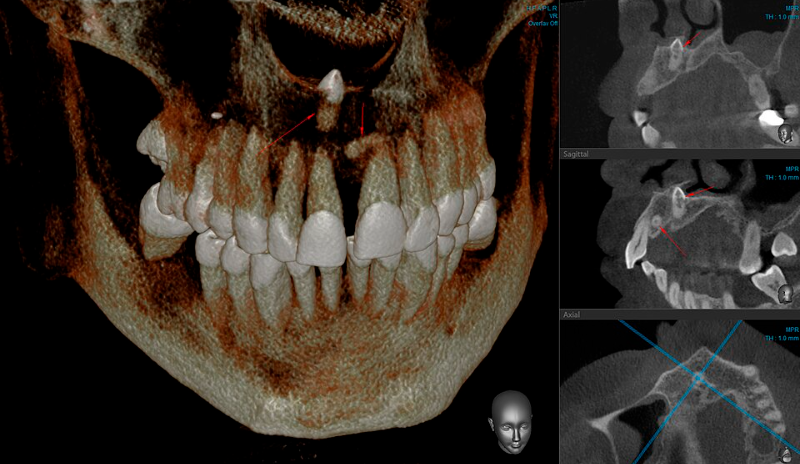

La hiperdoncia ocurre cuando aparecen dientes adicionales en la mandíbula o en el maxilar superior. Estos dientes extra pueden crecer en diferentes posiciones, incluso ocultos dentro del hueso. En algunos pacientes apenas se detecta uno adicional, mientras que en casos más extremos pueden aparecer varios al mismo tiempo.

Las imágenes radiográficas suelen revelar situaciones sorprendentes. A veces los dientes adicionales permanecen atrapados dentro del hueso y solo se detectan cuando comienzan a afectar el crecimiento normal de los demás dientes.